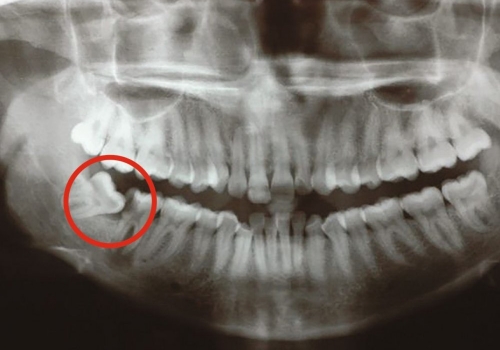

Normal halda insanın diş sırasında hər çənədə iki ədəd olmaqla, ümumilikdə dörd agıl dişi mövcuddur. Ağıl dişinin çıxması bəzi şəxslərdə heç bir kliniki əlamət və ya şikayətə səbəb olmasa da, bir çox hallarda müəyyən kliniki əlamətlərlə öyünü biruzə verir. Bu əlamətlər əsasən çənənin arxa tərəfində təzyiq, çənəni açıb baglama əsnasında agrı və məhdudlaşma kimi özünü göstərə bilir. Bu hallarda mütəxəssis konsultasiyasının önəmi olduqca böyükdür. Belə ki müayinə zamanı cərrah-stomatoloq kliniki və radioloji dəyərləndirmə apararaq dişin dogru pozisiyada yerləşib yerləşmədiyi, dişləmə çıxma ehtimalını, agıl dişinin çənəyə görə ölçüsü və çənə darlıgı kimi durumları dəyərləndirərək tətbiq edilməli olan müalicə taktikasını müəyyən edir.